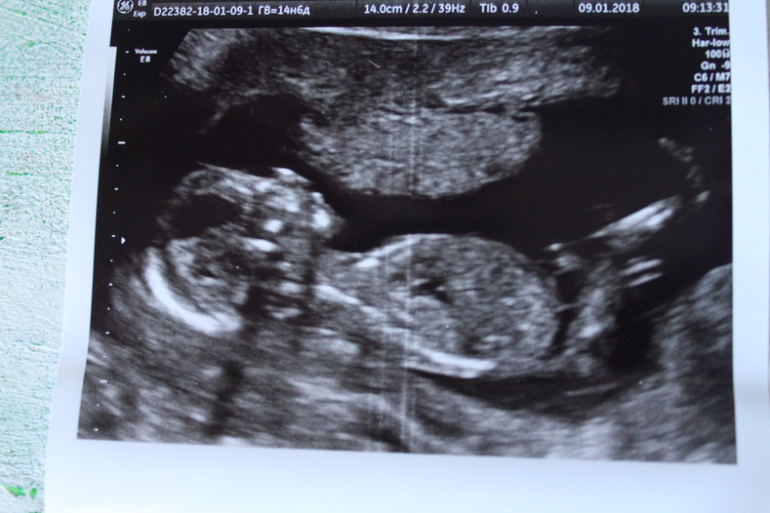

Узи 14 недель девочка